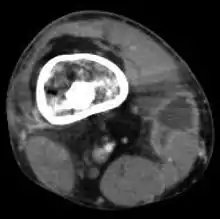

Radiographs and CT are the initial method of diagnosis, but are not sensitive and only moderately specific for the diagnosis. They can show the cortical destruction of advanced osteomyelitis, but can miss nascent or indolent diagnoses.[21]

Confirmation is most often by MRI. The presence of edema, diagnosed as increased signal on T2 sequences, is sensitive, but not specific, as edema can occur in reaction to adjacent cellulitis. Confirmation of bony marrow and cortical destruction by viewing the T1 sequences significantly increases specificity. The administration of intravenous gadolinium-based contrast enhances specificity further. In certain situations, such as severe Charcot arthropathy, diagnosis with MRI is still difficult.[21] Similarly, it is limited in distinguishing bone infarcts from osteomyelitis in sickle cell anemia.[22]

Nuclear medicine scans can be a helpful adjunct to MRI in patients who have metallic hardware that limits or prevents effective magnetic resonance. Generally a triple phase technetium 99 based scan will show increased uptake on all three phases. Gallium scans are 100% sensitive for osteomyelitis but not specific, and may be helpful in patients with metallic prostheses. Combined WBC imaging with marrow studies have 90% accuracy in diagnosing osteomyelitis.[23]

Diagnosis of osteomyelitis is often based on radiologic results showing a lytic center with a ring of sclerosis.[12] Culture of material taken from a bone biopsy is needed to identify the specific pathogen;[24] alternative sampling methods such as needle puncture or surface swabs are easier to perform, but do not produce reliable results.[25][26]